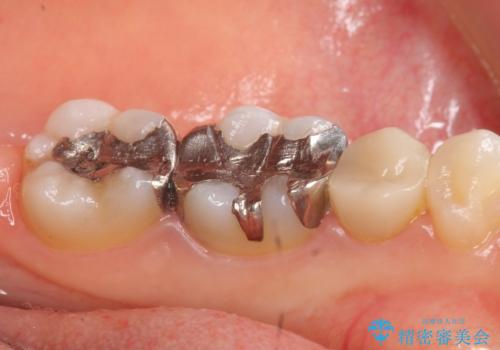

- 左下奥歯の銀歯が気になると来院された方の症例です。

左下7はセラミックインレーによる修復を行い、左下5、6はオールセラミッククラウンによる補綴を行いました。

セラミックインレーについて

当院のセラミックインレーはemaxという強度と審美性に優れた材料を使用しています。

またプレス方式でインレーを製作しているため、削り出しで製作するCADCAMより優れた適合性も持ち合わせており、虫歯が再発しにくい修復物です。